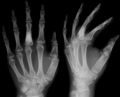

X-ray showing calcified enchondromas localized in finger a 37-year-old patient affected with Ollier disease

On radiographs, streaks of low density are seen projecting through the diaphyses into the epiphyses of the long bones, due to ectopic cartilage deposits. With age, the cartilage may calcify in the typical "snowflake" pattern.